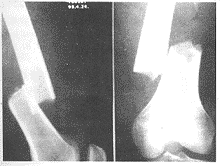

图2 股骨干骨折术前正、侧位X线片

图3 股骨髁上交锁钉术后正、侧位X线片